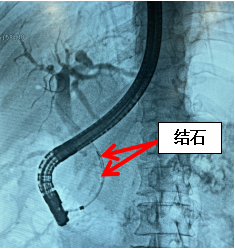

術(shù)中造影顯示膽總管下段多發(fā)結(jié)石

3個月后患者一般情況良好,再次入院行第二次ERCP術(shù),取出膽道支架后進行球囊擴張,用取石網(wǎng)籃去除較多黃色碎狀結(jié)石并清理膽道;先后取出黃褐色橢圓形結(jié)石一枚及較多泥沙樣結(jié)石,結(jié)石最大直徑1.5cm!取石后造影膽道引流通暢。